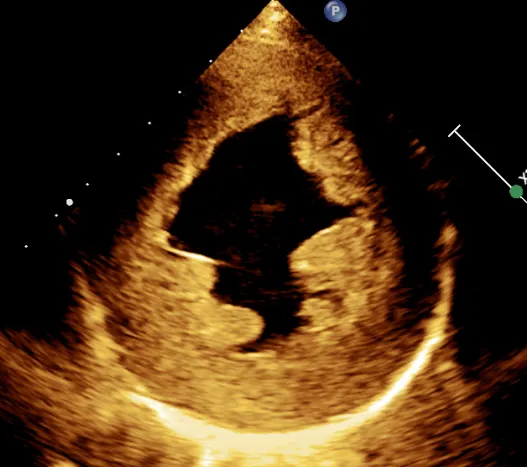

主要表现为心腔扩大,以左心扩大为主或全心扩大;左室球形变(图 2 ),室壁运动幅度弥漫性减低,相对室壁薄,瓣口开放幅度小,呈经典的「 大心腔、小开口 」改变。

图 2 四腔心切面显示,左室呈球形扩大